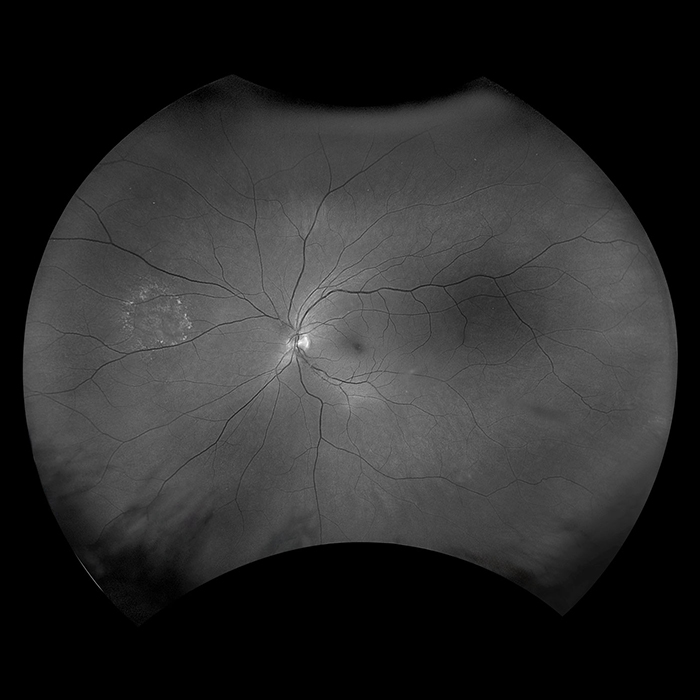

Daytona produces a 200° single shot optomap retinal image of unrivaled clarity in less than ½ second. This fast, easy, patient-friendly, ultra-widefield imaging technology was designed for healthy eye screening and has been shown to improve practice flow and patient engagement.

Why Daytona?

optomap has been shown to enhance pathology detection and disease management and to improve clinic flow. The Daytona system is the most widely used true UWF imaging device.

optomap Image Modalities

- color rg

- Sensory Retina

- Choroidal

- green af